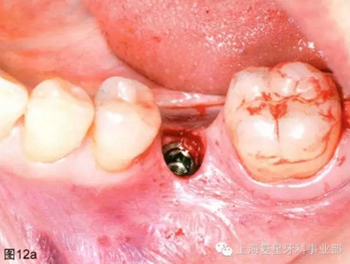

通過(guò)導(dǎo)板的引導(dǎo),以15prm,50Ncm旋入種植體。一旦種植體到達(dá)最后的深度(圖12a),去除種植手機(jī)和攜帶器,然后將一個(gè)愈合基臺(tái)(BioHorizons,直徑4.5毫米×長(zhǎng)3毫米)擰在種植體上(圖12b)。軟組織打孔器取出的軟組織進(jìn)行結(jié)締組織移植,然后放置在一個(gè)頰楔上獲得一定體積和厚度的角質(zhì)化軟組織(圖12c)。無(wú)需縫合。術(shù)后拍攝X片,對(duì)種植體的最終位置進(jìn)行評(píng)估。

圖12a:種植體放置最終的位置上